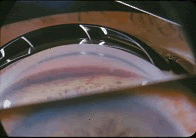

- [材料题] 患者,女性,70岁,高血压史5年,3个月前右眼突然视力下降,外院诊断为右眼缺血型视网膜中央静脉阻塞,予药物治疗。2天前,患者出现右眼胀痛。检查右眼视力数指,角膜上皮水肿,前房不浅,虹膜红变,晶状体尚透明,眼压40mmHg。

- 单项选择题1.(如图)最可能的诊断是 ( )

A、急性闭角型青光眼

B、新生血管性青光眼

C、开角型青光眼

D、血影细胞性开角型青光眼

E、慢性闭角型青光眼